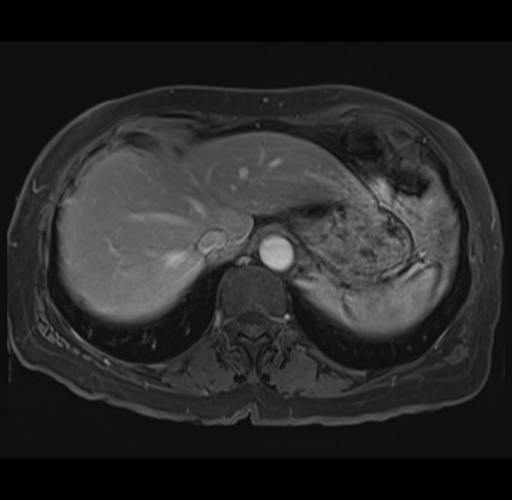

MRI T1